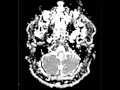

Brainstem Glioma

8-year-old female with a history of dysarthria and seizures. There is an infiltrative T1-hypointense, T2/FLAIR hyperintense mass within the left brachium pontis, left dorsal pons, and left dorsal medulla. The lesion demonstrates nodular and more curvilinear regions of enhancement without diffusion restriction. The differential diagnosis includes brainstem glioma, pilocytic astrocytoma, ependymoma and medulloblastoma. The findings are most compatible with a diffuse brainstem glioma, which account for about 1/4 of all posterior fossa tumors, and present most commonly between 7 and 9 years of age. Common clinical presentations include ataxia, cranial nerve palsies, long tract signs and hydrocephalus. Lesions can be associated with neurofibromatosis-1. Treatment and prognosis depends on tumor type and location.